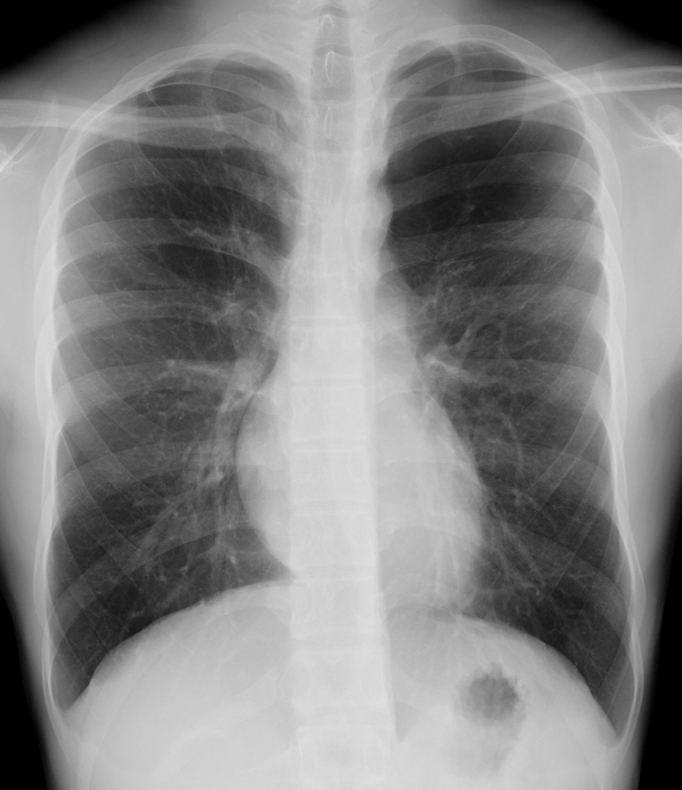

A Case of Asymptomatic Juvenile Emphysema.